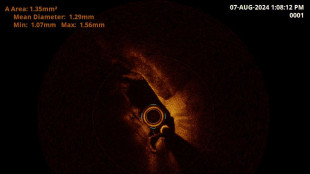

Alleanza Singapore, Stanford e Zeiss per chirurgia degli occhi

20 milioni di dollari di finanziamenti per i prossimi tre anni